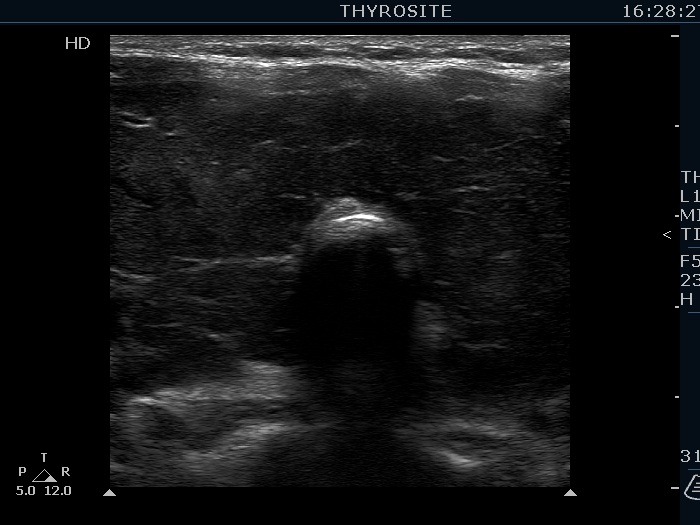

Consecutively operated patients with autoimmune thyroid disease - case 41 (1446) (ultrasonographic picture 10)

Isthmus, transverse scan. The isthmus is broadened.